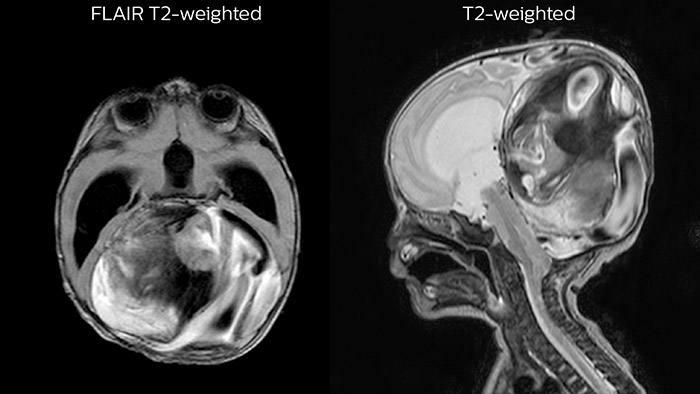

Since scan times of 3D scans can be significantly shortened thanks to Compressed SENSE, the MRI team is performing more 3D scans than before. “The advantage of 3D scanning is that we capture one high resolution sequence, but we can reconstruct images in any orientation, even after the scan, when looking at the images for diagnosis. Having this ability to view any crosssection we need in high resolution, can make re-scanning unnecessary,” says Dr Junge. “We are currently optimizing our routine head examination to include more 3D scans, including T1- weighted, T2-weighted and FLAIR.”

Hydrocephalus post hemorrhagic Both pictures show a ventriculoperitoneal shunt. With our previous scanner our hydrocephalus protocol needed about 25 min. With Ambition the examination time is about 14 min. including a CSF PCA sequence to show flow in the aqueduct.

Leukodystrophy in a teenager

Rostral meningitis and arachnoiditis Both images are from the same 3D T1-weighted post contrast sequence in a newborn, under treatment.